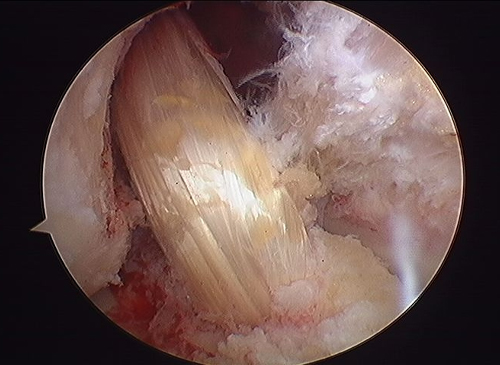

Before

-

-

After

- 최소 절개로 대퇴골과 경골의 병변 부위에 구멍을 내줍니다.

- 터널 구멍을 이용해 이식건을 통과시켜 넣습니다.

- 삽입된 인대를 당긴 후 양측에서 고정하여 새로운 인대 조직이 원래의 인대 강도를 유지하도록 잡아줍니다.